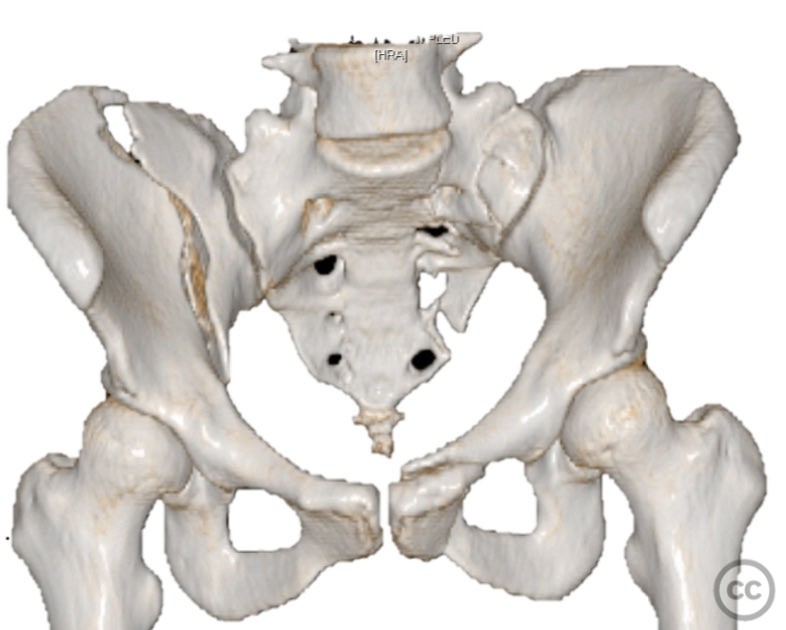

Clinical and radiological findings:  A 26-year-old female sustained a closed pelvic ring injury following a motor vehicle accident. She was hemodynamically stable, neurologically intact, and had no other associated injuries. Skin integrity was preserved. Initial management included pelvic binder application and 10 pounds of distal femoral skeletal traction. Portable AP pelvic radiograph demonstrated a left-sided sacral fracture with associated ipsilateral iliac wing and pubic ramus fractures, consistent with an AO/OTA 61-B2 (lateral compression type II) injury pattern.

Anatomical surgical approach:  The left sacral fracture was addressed first via percutaneous placement of iliosacral screws under fluoroscopic guidance. An anterior approach to the iliac wing was performed via a longitudinal incision along the crista iliaca, subperiosteal dissection to expose the fractura alae ossis ilii, followed by debridement, reduction, and temporary clamping. Definitive fixation was achieved with two 7mm diameter cannulated fully threaded medullary screws placed across the iliac crest and pelvic brim into the corpus ossis ilii. The left ramus ossis pubis fracture and overall cingulum pelvicum were assessed intraoperatively with fluoroscopy for residual instability.

Intraoperatively, minimal residual deformity of the left hemipelvis was noted after traction and positioning. The sacral fracture was stabilized first with iliosacral screws. The anterior iliac exposure allowed for direct visualization, cleaning, reduction, and clamping of the iliac wing fracture prior to screw fixation. After fixation, intraoperative fluoroscopic stress examination demonstrated stability of the left pubic ramus fracture and overall pelvic ring, obviating the need for further anterior fixation.